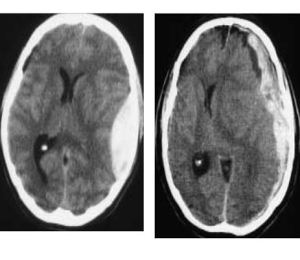

Qui di seguito sono riportate schematicamente le sedi, dove maggiormente si localizzano gli ematomi e alcune immagine di TAC del cranio che mostrano alcune lesioni cerebrali.

Ematoma extra durale, ematoma sub-durale emorragia intracerebrale